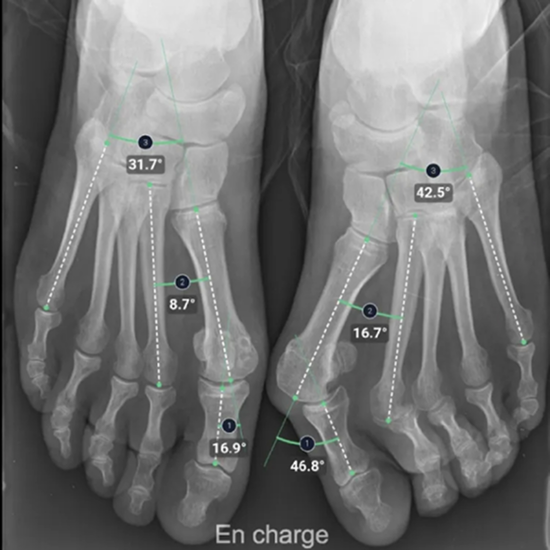

BoneMetrics automatically performs standard measurements for the feet, legs, pelvis/hips, and spine.

Through accurate point placement and easily understandable displays, the introduction of the software allows you to direct your attention to more critical tasks.

By introducing AI-supported standardization, variability can be reduced and reproducibility can be ensured.

Clinical studies prove that BoneMetrics matches the expertise of MSK radiologists, enabling your practice to provide the best possible service to patients.